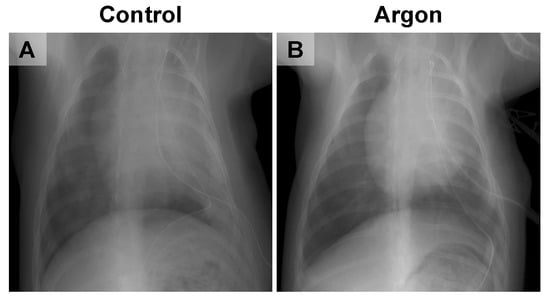

3.2. Argon Inhalation Reduces Pulmonary Infiltrates After IRI